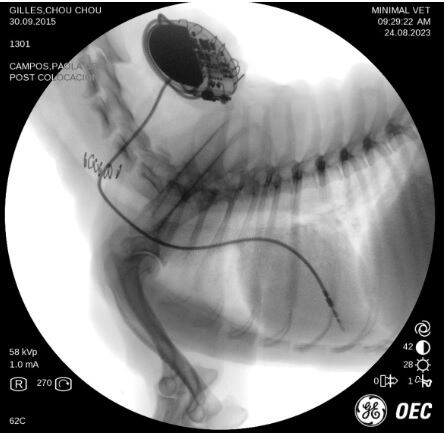

“El pasado 23 de agosto se le puso a Chou Chou el marcapasos, fue una operación que duró una hora y todo salió perfecto. La dejamos en observación y reposo 24 horas y después se la devolvimos a don Eric.

“El pasado lunes (25 de setiembre) la perrita volvió para la valoración del mes y todo está perfecto. El primer marcapasos de Centroamérica se puso con un éxito total, confirmamos que el marcapasos lo ocupa el 50% del tiempo y que no se ha vuelto a desmayar”, explica la doctora Campos.

“El marcapasos que se le puso a Chou Chou tiene un diseño pequeño y ergonómico llamado fisiocurve de la marca Medtronic, el cual permite que se acomode de forma excelente debajo de la piel. Además, está hecho con materiales especiales que evitan que el cuerpo lo rechace.